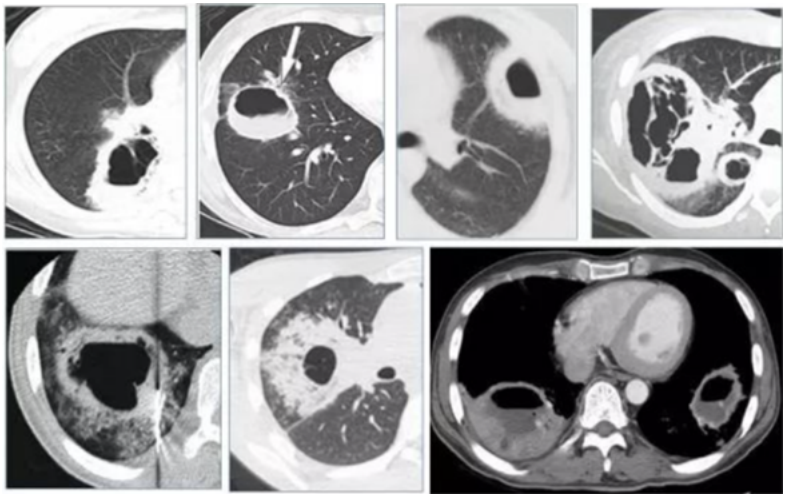

糖皮质激素的使用在其他病种中也被认为是IPA的危险因素,在重症流感中也不例外,有研究表明入ICU前系统性应用大剂量糖皮质激素是继发IAA的独立危险因素。除了重症流感,患者可能还会合并其他基础疾病,尤其是可以影响患者免疫状态的基础疾病,可能也是IAPA的危险因素。病例1::男,15岁,学生;主因“发热、干咳16天,加重伴呼吸困难8天”入院。既往体健,无基础病。入中日医院MICU时间为2018年1月16日,死亡时间为2018年1月26日。患者16天前(2017年12月30日)出现发热,体温39.0℃,伴干咳、咽痛。8天前(2018年1月7日)出现呼吸困难。血气分析示Ⅱ型呼吸衰竭,WBC 24.1×109/L,NE% 90%,PCT 3.3 ng/ml。不断升级抗细菌治疗,效果不佳:头孢曲松→亚胺培南、阿奇霉素、利奈唑胺。7天前(2018年1月8日)确诊乙流,加用帕拉米韦+奥司他韦。2天前(2018年1月13日):血GM试验测值增高,痰培养烟曲霉,诊断IAPA,加用伏立康唑。2018年1月15日转入中日医院呼吸与危重症医学科MICU。2018年1月8日胸部CT(起病1周余)提示气压伤非常严重,以及沿气道分布的斑片和小结节。此时的影像学提示曲霉感染已经显而易见(图1),但尚未得到病原学证据的支持,因此外院当时并未予抗真菌治疗,延迟抗真菌治疗也是导致患者预后不良的重要原因之一。1月15日(转入中日医院MICU后)气管镜检查,镜下可见气道狭窄和黏膜充血水肿均较明显,表面大量白苔,触之易出血(图2)。此时除了曲霉感染,BALF病原学还发现合并了CRAB感染。患者影像学快速进展,1月15日胸部CT显示双肺弥漫性沿支气管血管束分布的结节影、斑片影、厚壁空洞及片状实变(图3)。1月22日胸部CT显示双肺病变明显进展,结节、斑片融合为大面积实变影(图4)。最终患者因CRAB血流感染导致感染性休克,后期又并发脓毒性心肌病,最终去世。病例2::女,65岁,退休。间断干咳伴发热10天,加重伴呼吸困难4天。既往2型糖尿病史35年,使用精蛋白生物合成人胰岛素注射液(预混30R)治疗,血糖波动在7~8 mmol/L。患者入ICU时间为2018年2月4日,出ICU时间为2018年4月19日。10天前(2018年1月25日)“感冒”后出现干咳,伴发热,体温最高37.8℃。7天前(2018年1月28日),血常规:WBC 12.49×109/L,NEU% 87.5%,LYM% 7%,予莫西沙星。1月30日复查血常规:WBC 23.88×109/L,NEU% 91.5%,LY% 4.6%,调整抗生素为头孢噻肟+莫西沙星。4天前(1月31日)呼吸困难加重,SpO2(未吸氧)88%,复查血常规:WBC 37.04×109/L,NEU% 93.7%,LYM% 1.7%,PCT 1.79 ng/ml,痰涂片可见真菌孢子及菌丝。3天前(2月1日)咳痰费力,SpO2降至71%,开放气道吸痰过程中心率降至32次/min,立即心肺复苏,气管插管球囊辅助通气,约12 min患者自主心率恢复,接呼吸机辅助呼吸,经气道可吸出大量黄色黏痰,痰流感病毒核酸阳性。1月31日胸部CT示:沿支气管血管束分布的斑片和实变影(图5)。气管镜下可见充血、水肿,曲霉特征性假膜相对较少(图6)。

图6 支气管镜下表现

2月13日复查胸部CT(抗真菌治疗14天)显示影像学较前好转(图7)。患者病程中也经历了院感、肺外脏器支持等,病情最终好转出院。(1)一般情况:流感合并曲霉感染患者, 男性居多, 年龄大, 基础病情更加严重, 伴有免疫抑制因素(例如: 肿瘤、免疫抑制剂、激素)。(2)起病时间较早(入ICU早期),入ICU至IAPA诊断的平均时间<72小时(3天),短于COVID-19相关肺曲霉病(CAPA)4~13天,流感至IAPA诊断时间为(13±7)天。(3)临床症状/体征不典型:IAPA的临床表现无特异性,可表现为发热、咳嗽、呼吸困难、病情加重且对现有治疗无效。部分患者可能出现咳黑褐色痰或咯血,并且有致死性大咯血风险。CAPA和COVID-19相关肺毛霉病(CAPM)患者发展为重症需入住ICU的比例更高。此外,患者常合并呼吸衰竭/ARDS、急性肾损伤(AKI)、感染性休克。(4)实验室及影像学检查:实验室检查有一项比较重要的提示,IAPA患者可能会因为炎症反应强烈而导致WBC非常高,但PCT一般不会明显升高,淋巴细胞常明显降低。影像学表现有其特点(如前所述)。(5)独立危险因素:ICU早期WBC明显增高(>10×109/L)、入ICU后应用激素、CT特征表现(多发结节、空洞)是IAPA的独立危险因素。但仍需大样本量、多中心的病例对照研究进一步验证。从上述两个病例可以发现,由于患者的症状、体征、实验室检查大部分不特异,且常被伴发的流感及混合的细菌感染所掩盖,因此IAPA的早期诊断较困难。微生物学依据是诊断IAPA的金标准,而在拿到微生物学证据之前,影像学和气管镜检查可以帮助我们寻找蛛丝马迹,在临床上具有重要意义及提示作用,有助于早期诊断。因此,熟悉其表现尤为重要。(1)微生物学证据:2020年欧洲医学真菌学协会/国际人类和动物真菌学学会(ECMM/ISHAM)发布的关于CAPA的定义及共识声明中提到的检测方法以及cut off值可供参考,包括:①BALF直接镜检阳性、BALF培养/PCR阳性,血GM/LFA>0.5,BALF-GM/LFA≥1;②血浆/血清/全血PCR阳性≥2次;③单次BALF PCR阳性且CT<36;④单次血浆/血清/全血PCR阳性,且单次BALF-PCR阳性(不要求CT值)。(2)CT表现:CT在IAPA的早期诊断中具有重要的提示意义。病变沿支气管血管束分布;合并曲霉感染患者有明显的气道受累,包括气道壁增厚、气道狭窄,以及树芽征;典型的病变性质是结节和斑片,空洞及新月征不多见,但有特异性;大片实变影也相对特异,且提示预后差。(3)气管镜下表现:气管镜也是一种非常重要的早期诊断IAPA的手段,可以发现气管镜下典型的假膜。除了观察气道病变的特点及范围,还可以获得高质量的下呼吸道标本,有助于提高真菌培养阳性率,获取及动态监测BALF-GM试验结果。此外,气管镜还能够进行痰液引流。对于气道病变非常严重或局限的患者,气管镜还可以进行气道内给药。值得一提的是,来自欧洲7个国家和美国以及中国台湾等地的29名专家提出了IAPA诊断专家共识,2023年已发表在Intensive Care Medicine 杂志上,将IAPA分为曲霉菌性气管支气管炎及侵袭性肺曲霉病,高度强调了气管镜的重要性,无论是气管镜镜下表现还是气管镜获取BALF标本进行GM试验或真菌培养都是共识中的重要条目,可能有助于IAA的早期诊断。